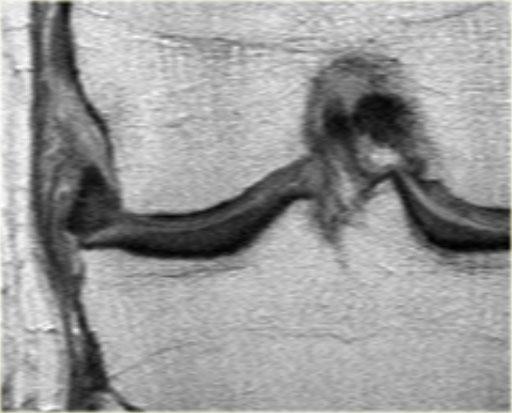

Cùng ca bệnh trên với hình ảnh mặt phẳng sagittal.

Lưu ý phần bị rách của sụn chêm chạy ra phía trước qua hố gian lồi cầu (các mũi tên)

- Thông thường chỉ có hai cấu trúc chạy trong hố gian lồi cầu. Ở đây chúng ta thấy dây chằng chéo sau bình thường.

- Dây chằng chéo trước bình thường.

- Phần bị rách của sừng sau như là ‘cấu trúc thứ ba’

trong hố gian lồi cầu. - Phần bị rách chạy ra phía trước.

- Phần bị rách nhập vào sừng trước và giả tạo hình ảnh rách dọc ở sừng trước.

Lưu ý phần còn lại nhỏ của sừng sau.